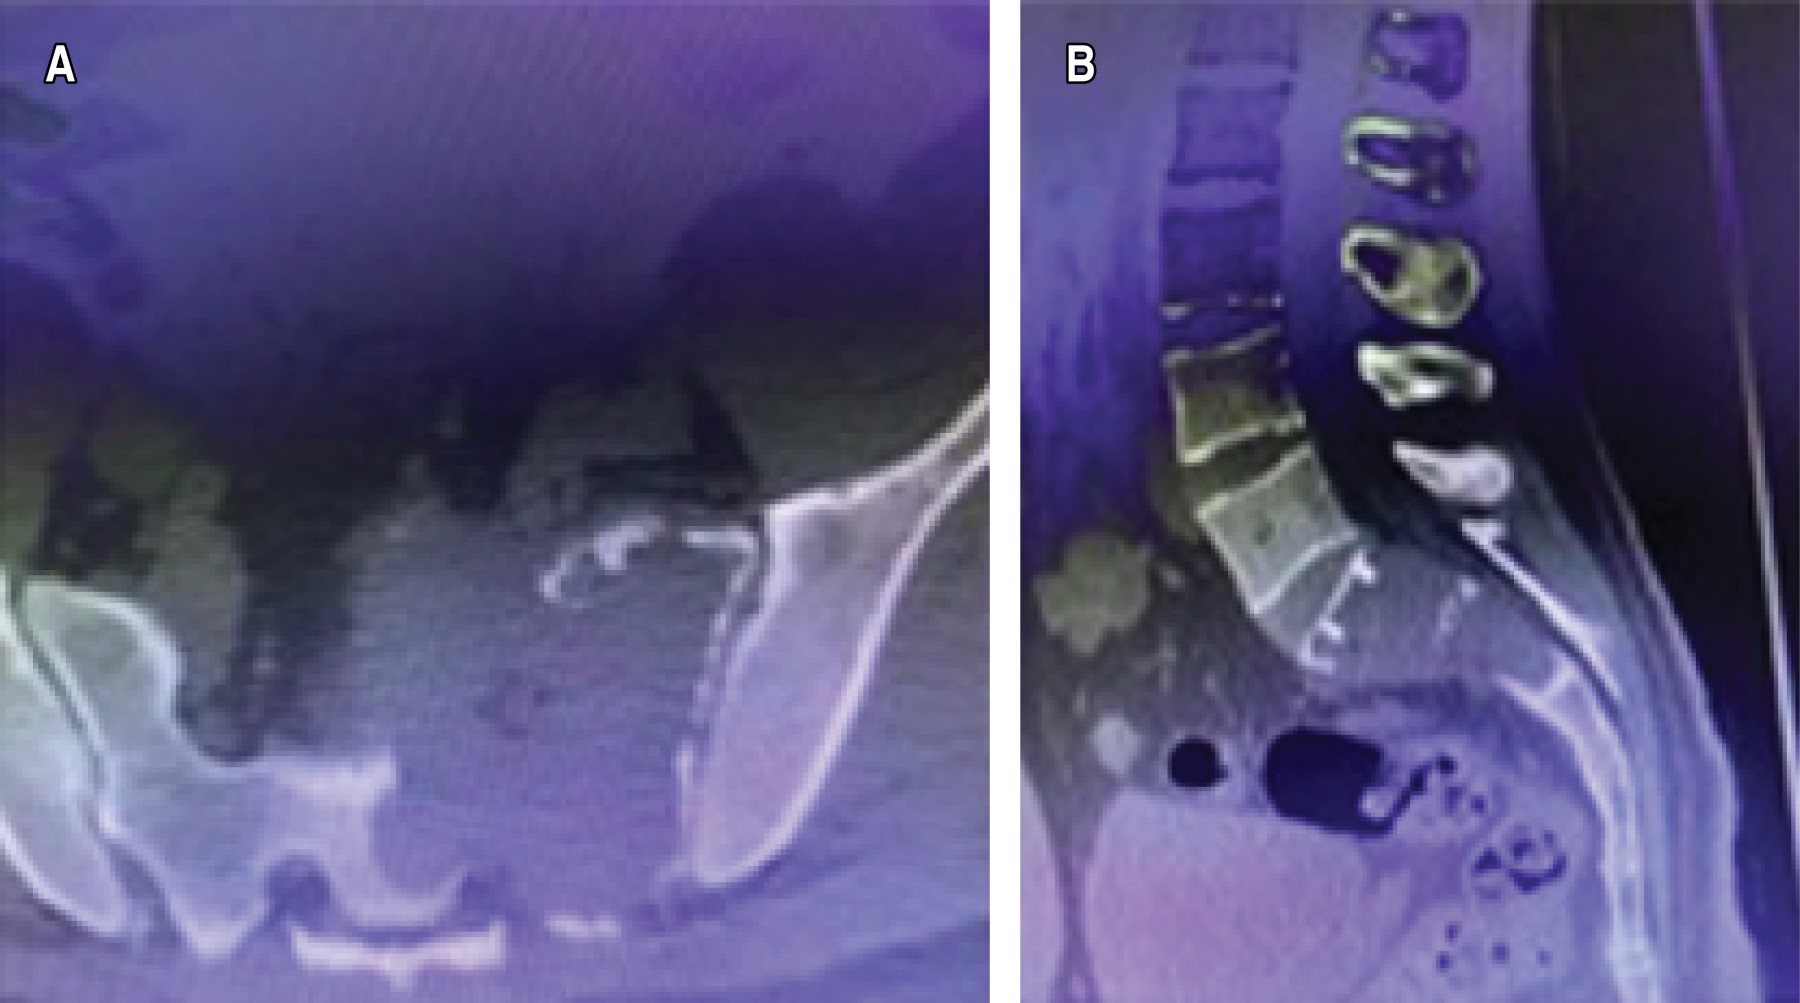

Los laboratorios no mostraban alteraciones. En el estudio de radiografía simple en proyección anteroposterior de pelvis se identificó osteólisis que se limitaba al sacro; en la tomografía computarizada, imagen lítica que compromete S1 y S2 del sacro respetando el disco intervertebral en los cortes sagitales, de aspecto quístico y expansivo y corticales adelgazadas esclerosadas, pero sin solución de continuidad ni invasión de tejidos adyacentes (Figura 4).

La resonancia magnética mostró un crecimiento infiltrativo en S1-S2 y ligeramente expansivo con preservación de la estructura sacra y respetando tejidos blandos, apreciándose en forma difusa y homogénea, con señal hipointensa en la secuencia T2 (Figura 5A y